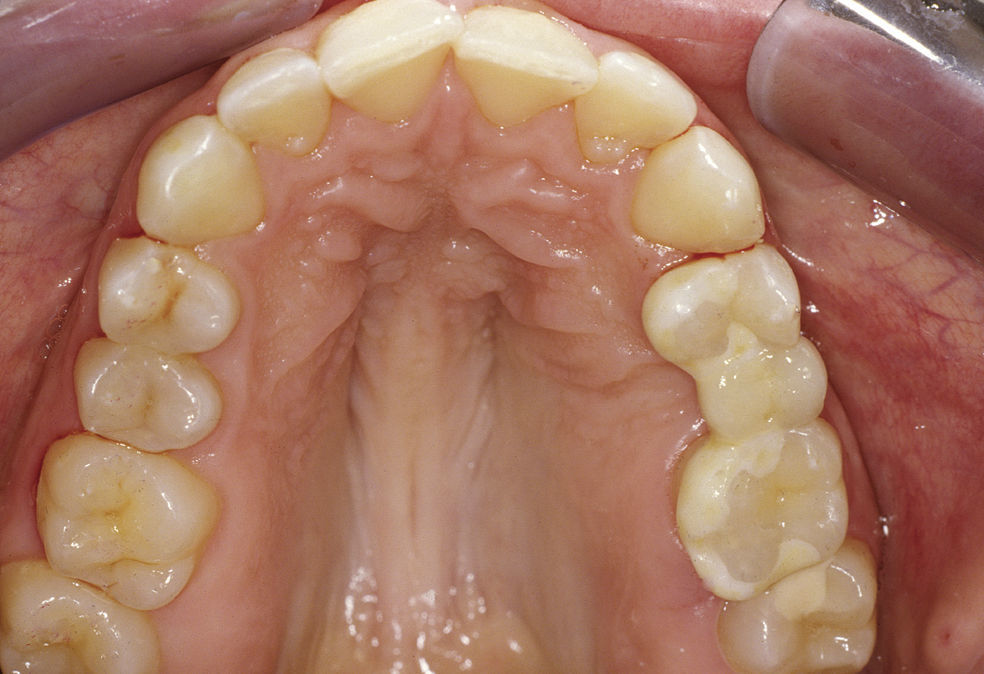

Exposición del casoSituación de partidaLa paciente de 25 años se presentó en el año 2008 en el departamento protésico de nuestra clínica antes de la extracción de un resto radicular en la región 25 y ex- presó el deseo de un cierre convencional del espacio. Al padecer asma bronquial, la paciente estaba bajo tratamiento con prednisolona oral (Decortin H). No se observaron ni anamnésica ni clínicamente indicios de un trastorno funcional, de bruxismo ni de parafun- ciones orales. Sin embargo se observó una gingivitis pronunciada. Pese a la motivación y la remotivación repetida, la mejora de la higiene oral a lo largo del tra- tamiento fue limitada. En cualquier caso, para la pa- ciente se habría contemplado como medida provisional una construcción extraíble para el cierre del espacio. La paciente rechazó una restauración implantosoporta- da por miedo a la intervención y por motivos econó- micos. Además, el espacio disponible sin una apertura ortodóncica previa del espacio habría resultado insufi- ciente desde los puntos de vista quirúrgico y estético (figs. 1–4). La paciente tampoco deseaba un cierre ortodóncico del espacio. Respetando sus deseos y en virtud del estado básicamente intacto de los dientes de- limitadores del espacio, tras un asesoramiento exhaus- tivo se optó por una opción de tratamiento poco invasi- va mediante un cierre del espacio adhesivo de cerámica sin metal consistente en un puente adhesivo de tres piezas de dióxido de zircón recubierto, realizado en un innovador diseño experimental. Se explicó claramente a la paciente que se trataba de un tipo de tratamiento que se encontraba todavía en fase experimental y cuyo pronóstico todavía no estaba en absoluto claro.

Los dientes pilares 24 y 26 eran vitales y periodontal- mente normales más allá de la gingivitis ya mencionada.

La obturación en el diente 26 llegaba radiológicamente hasta claramente por debajo del límite amelocementa- rio. El resto radicular afectado por caries en la región 25 apenas resultó apreciable durante el examen, ya que es- taba casi completamente cubierto por la encía. Radioló- gicamente se observó un aclaramiento apical. Así pues, en términos globales se daba la indicación para una ex- tracción, la cual se llevó a cabo sin demora y sin compli- caciones (figs. 5 y 6).